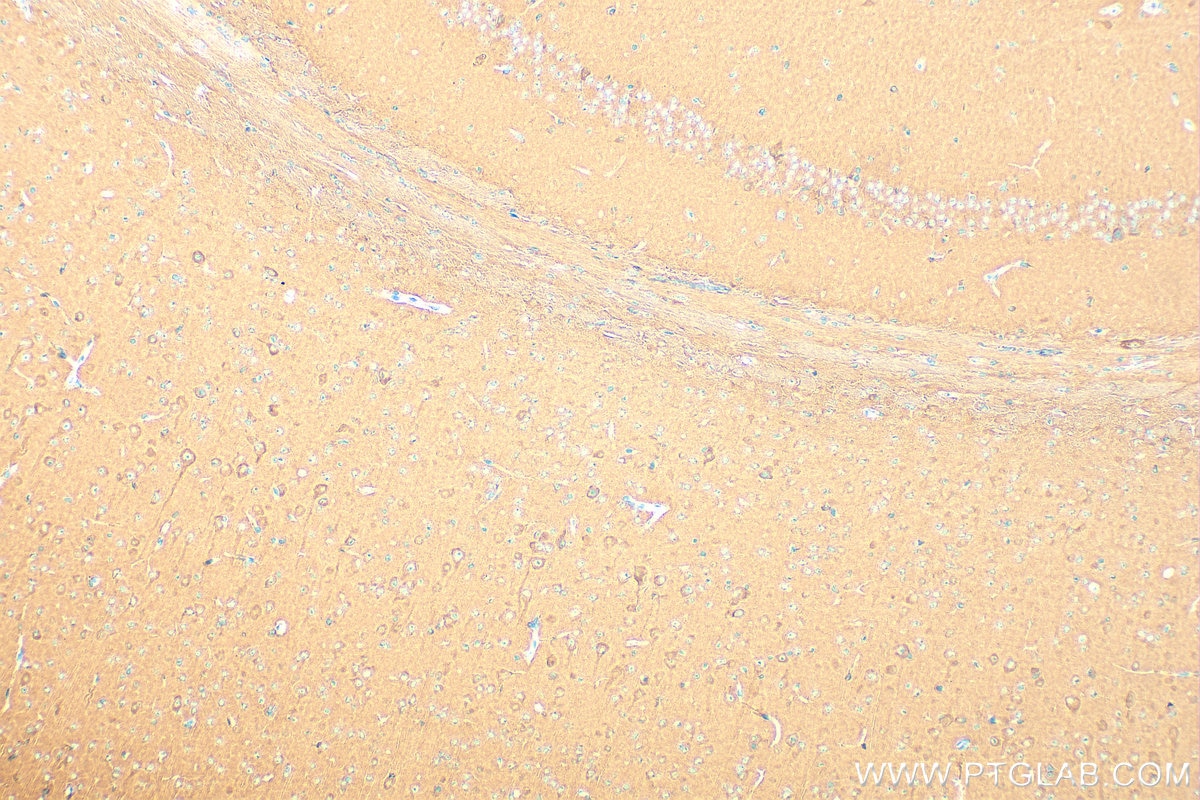

| Positive IHC detected in | mouse brain tissue Note: suggested antigen retrieval with TE buffer pH 9.0; (*) Alternatively, antigen retrieval may be performed with citrate buffer pH 6.0 |

| Immunohistochemistry (IHC) | IHC : 1:500-1:2000 |